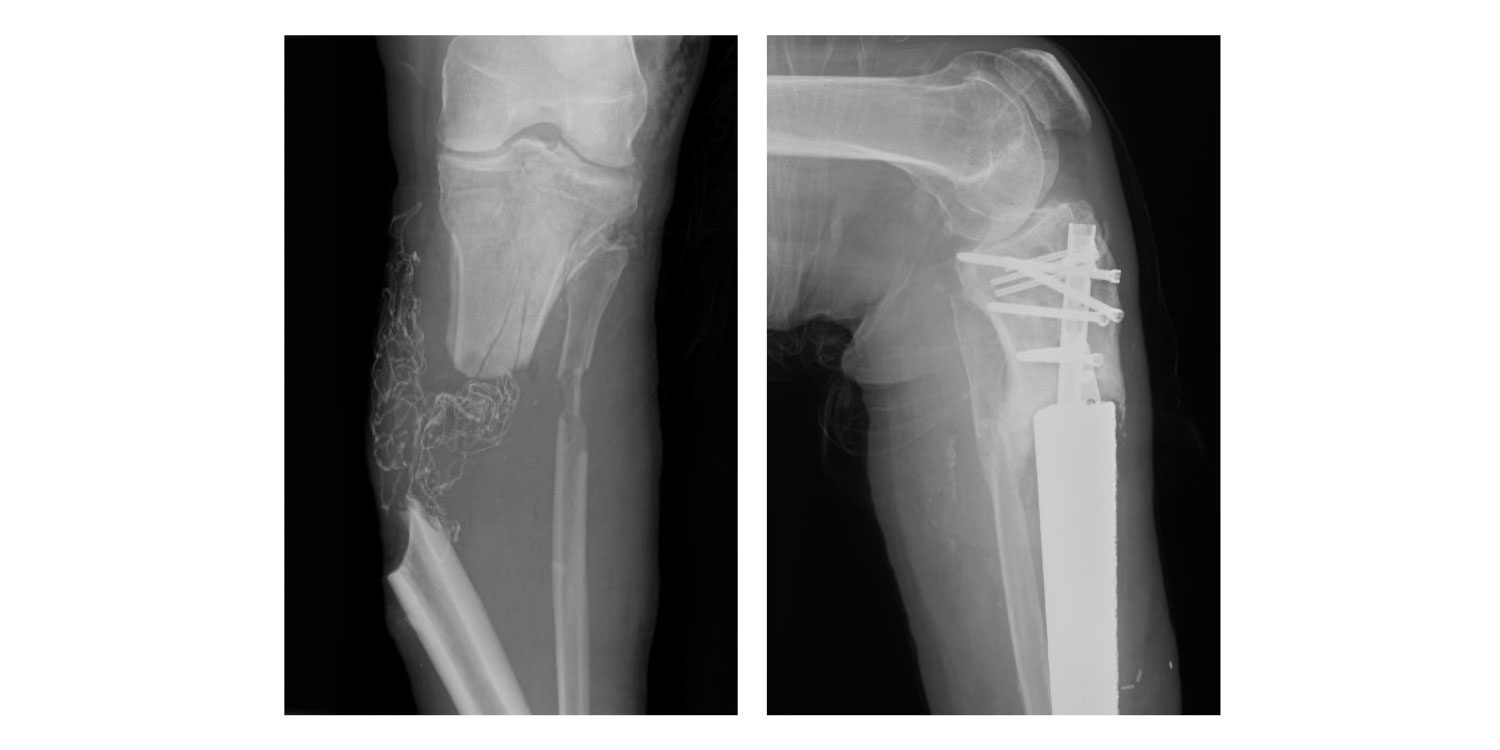

When DeShazo regained consciousness, he met Malcolm DeBaun, MD, an orthopaedic trauma surgeon at Duke Health, who would care for him for the next 18 months. “Bruce had a limb-threatening injury but because of the severity, he wasn’t a candidate for typical bone reconstruction procedures,” he said. At other institutions, this would have meant an above-the-knee amputation. But Dr. DeBaun knew there had to be a better option.

He collaborated with his colleague, Geoffroy Sisk, MD, a plastic and reconstructive surgeon at Duke Health, and a local company that creates individualized 3D-printed orthopaedic implants. “We needed a new solution for his problem because it was very complex,” said Dr. DeBaun.

After several meetings, the team had a plan. Although it came with risks and multiple surgeries, DeShazo -- an active man who wanted to stay that way -- accepted the doctors’ proposal. First, surgeries were performed to remove debris and temporarily stabilize the leg. Second, Dr. Sisk used advanced microsurgery to transplant two muscles from DeShazo’s back to his lower leg to cover and protect the the healing limb. Third, Dr. DeBaun replaced DeShazo’s lower leg bone (tibia) with a customized 3D titanium implant. DeShazo participated in intense physical therapy throughout the process, which took a year and a half.

During DeShazo’s seventh and final surgery, a 3D titanium rod was implanted to replace his lower-left leg and stabilize it with rods, plates, and screws. He’s returned to Roxboro, where he can once again enjoy life. “My life went back to pretty much normal, just a slower pace. I am so thankful because I didn’t think I would ever be able to walk again.” Dr. DeBaun agreed. “He’s super happy that he has a limb to stand on, and it's his own with a little bit of titanium augmentation. It’s miraculous.”